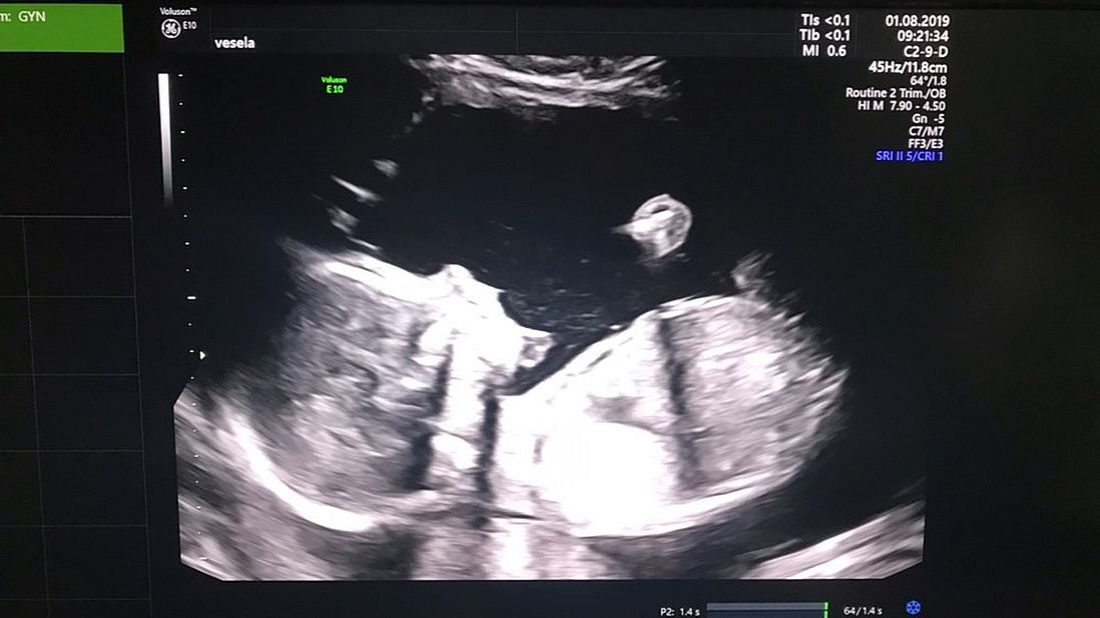

Káťa ve 22. tt – Karta v porodnici

TĚHULKA LIVE! KÁŤA Zdravím vás opět s dalším článkem. Počasí venku je krásně letní, ale začíná nám další školní, u nás tedy školkový rok. Takže víkend byl u nás ve znamení přípravy do školky. Nebylo tedy moc času dojímat se nad nenarozeným miminkem, i když jsem tedy stihla absolvovat kontrolu u mé lékařky.